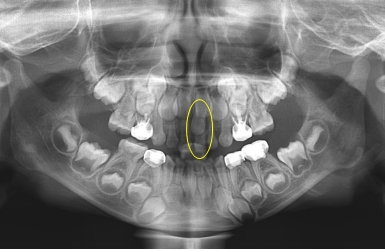

Á¤Áß°úÀ×Ä¡ÀÇ 75%´Â ¸Åº¹µÈ »óÅÂÀ̱⠶§¹®¿¡ ¸ð¸£°í Áö³»´Ù°¡,

X-ray ÃÔ¿µ¿¡¼ ¿ì¿¬È÷ ¹ß°ßµÇ´Â °æ¿ì°¡ ¸¹½À´Ï´Ù.

¾Õ´Ï°¡ ¹ú¾îÁö°í »ß¶Ô¾îÁ® Àִ ȯÀÚ¿¡¼ X-ray¸¦ ÃÔ¿µÇÏ¿´´õ´Ï °úÀ×Ä¡°¡ ¸Åº¹µÇ¾î ÀÖ´Â °ÍÀÌ º¸ÀÔ´Ï´Ù.

Ä¡¾Æ »Ñ¸® ¾ÕÂÊ¿¡ ¸Åº¹µÇ¾î ÀÖ´Â °úÀ×Ä¡·Î ÀÎÇØ ¾Õ´Ï »çÀ̰¡ ¹ú¾îÁö°í, ¿À¸¥ÂÊ ¾Õ´Ï°¡ »ß¶Ô¾îÁø ä·Î

¸ÍÃâÇÏ¿´½À´Ï´Ù.